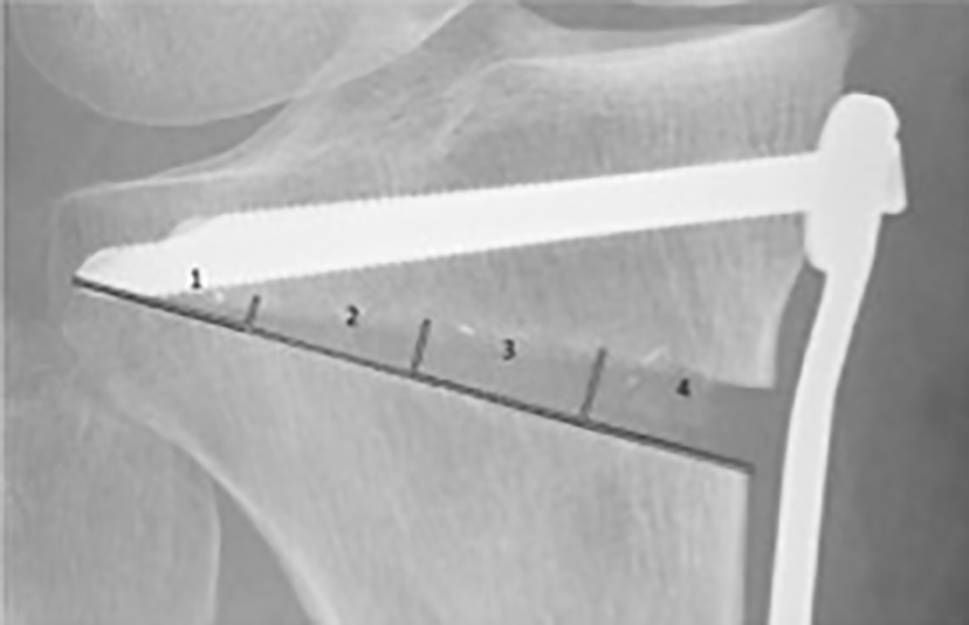

All radiographs were analyzed by three specialists (orthopedic surgeons). The analysis included assessment of the osteotomy gap (osteotomy length, length of fused osteotomy, medial width of osteotomy), sclerosis (0 = no sclerosis, 1 = mild sclerosis, thinner than half of the lateral cortex, 2 = sclerosis, equal or more than half of the thickness of the lateral cortex), trabecular structure (0 = none, 1 = sparse growth, 2 = trabecular ossification) and the score for gap healing as described by Schröter et al. [14]. For this score, the osteotomy length (A) and the length of the fused osteotomy are measured (B). The percentage of gap filling with new bone is the result of dividing distance B by distance A. To evaluate ossification and morphology of bone healing, the osteotomy gap was divided into four zones numbered from lateral to medial osteotomy site (see Fig. 2). In each zone, the non-ossified area was measured, using the imaging software Impax ® EE (Agfa HealthCare GmbH, Bonn, Germany).

Fig. 2

Division of gap into 4 zones for further radiological evaluation